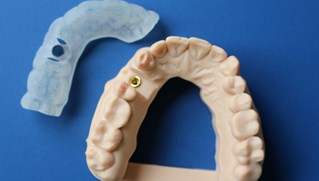

Inför operationen framställs en guideskena som underlättar operationen och ger oss en stor precision vid placeringen av titanskruven (fixturen)

Våra tandtekniker på "Fenix Dentalteknik" i Örebro framställer en krona.

Kronan kan antingen monteras som på bilden med en centrumskruv alternativt cementeras fast på en distans.